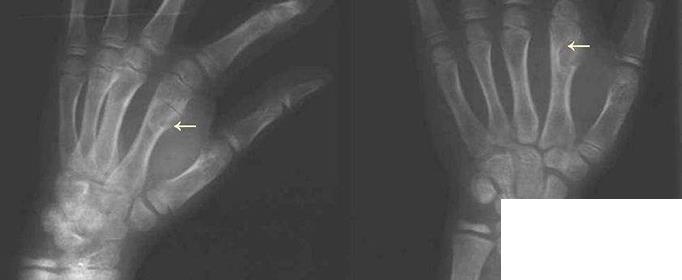

01Ollier病又叫多發(fā)內(nèi)生軟骨瘤病,是一種少見的非遺傳性良性腫瘤,由多數(shù)不對稱分布在骨內(nèi)的軟骨病灶及骨膜下沉積所致。在機(jī)體的長短管狀骨中、在肢體的單側(cè)或雙側(cè)均可發(fā)病。因Ollier在1899年首次描述本病,故又稱Ollier病。臨床出現(xiàn)可觸及的無痛性腫塊,常侵及手或足,造成病殘。本病有惡變的可能。

多發(fā)內(nèi)生軟骨瘤病是一種少見的非遺傳性良性腫瘤,因Ollier在1899年首次描述本病,故又稱Ollier病。臨床出現(xiàn)可觸及的無痛性腫塊,常侵及手或足,造成病殘。該病病因是多發(fā)內(nèi)生軟骨瘤病是骨骼發(fā)育過程中,由部分異位的骨骺板衍變而成。

多發(fā)內(nèi)生軟骨瘤病發(fā)病年齡在10歲以內(nèi),男性多于女性,在兒童時期出現(xiàn)癥狀,青春期出現(xiàn)明顯畸形,以后逐漸穩(wěn)定。臨床表現(xiàn)為出現(xiàn)可觸及的無痛性腫塊,可侵及手或足,造成病殘。病變侵及長管狀骨,使內(nèi)生軟骨不能正常骨化,骨骺板不能正常生長,肢體出現(xiàn)短縮彎曲而畸形。如前臂向尺側(cè)彎曲畸形、下肢膝外翻等。患者成年后腫瘤可停止生長。本病在成人可發(fā)生惡性變,惡變率為5%~25%。